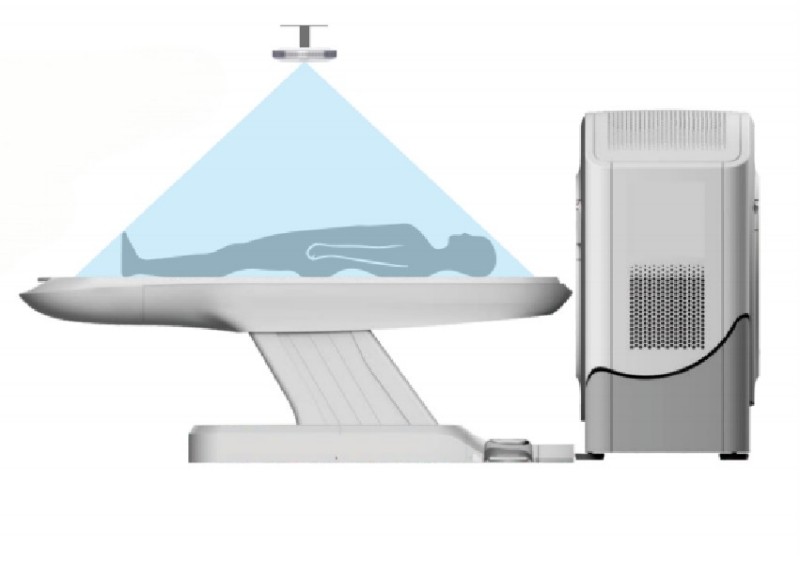

OCEAN 128S CT

● Prioritize dose care to enhance the scanning experience● 25 MHU LMB tube, empowered reliability, efficiency, and longevity

OCEAN 128S CT (128-slice)

25 MHU LMB tube, empowered reliability, efficiency, and longevity